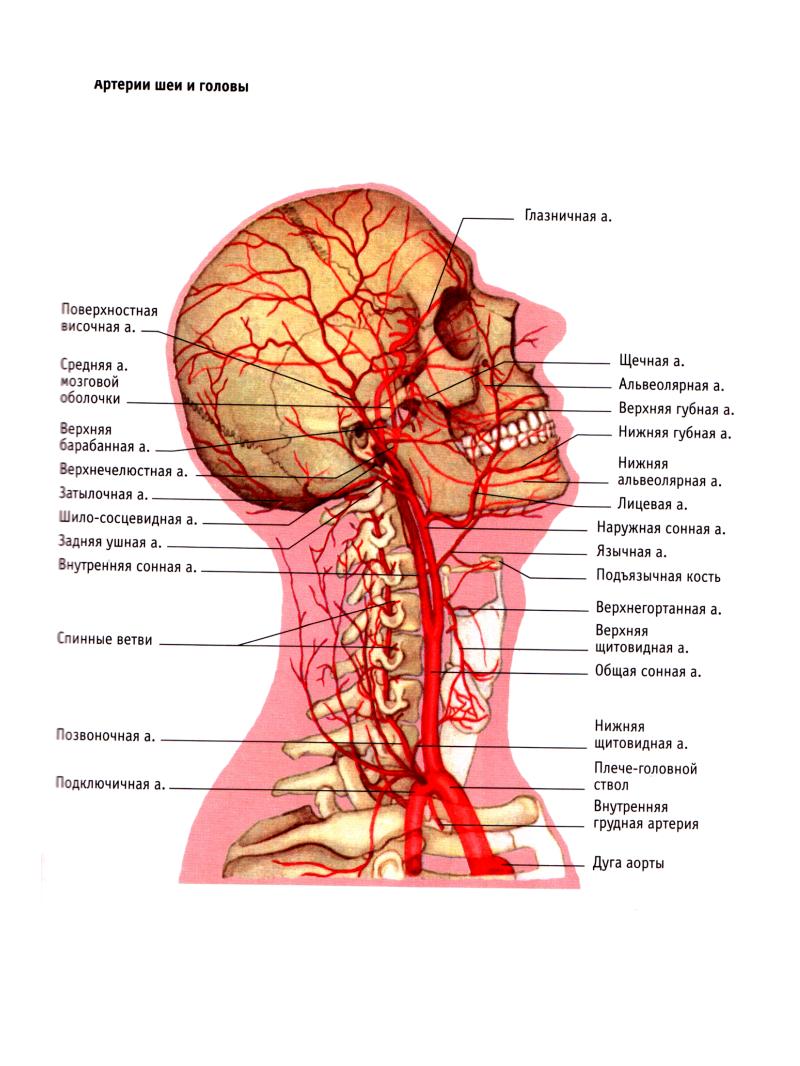

Анатомия внутренней яремной вены: КТ изображения